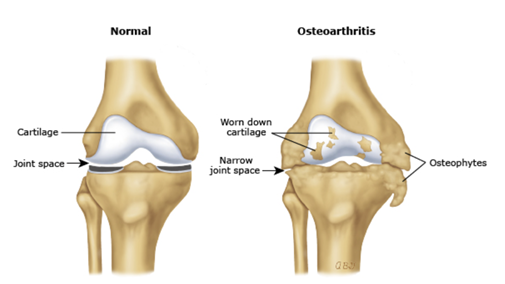

Osteoarthritis (OA) adalah penyakit degeneratif akibat kerusakan pada kartilago sendi, peradangan, dan pembentukan tulang baru di sekitar sendi. Hal ini dapat menyebabkan nyeri, kekakuan, hingga terbatasnya fungsi sendi.

PRP adalah plasma darah yang mengandung konsentrasi trombosit yang lebih tinggi dari plasma normal. Trombosit mengandung faktor pertumbuhan, protein, dan sitokin yang berperan dalam proses penyembuhan jaringan. Saat dokter menyuntikkan plasma ke dalam sendi yang terkena osteoarthritis, faktor-faktor pertumbuhan dalam trombosit akan merangsang proses perbaikan dan regenerasi jaringan. Mereka mendorong proliferasi sel-sel kondrosit dan matriks ekstraseluler, meningkatkan sintesis kolagen, dan mengurangi peradangan.

- Memperbaiki kartilago: Faktor pertumbuhan dalam PRP dapat merangsang regenerasi dan perbaikan kartilago yang rusak.

- Mengurangi peradangan: Komponen antiinflamasi dalam PRP dapat membantu mengurangi peradangan dan mencegah kerusakan lebih lanjut pada sendi.